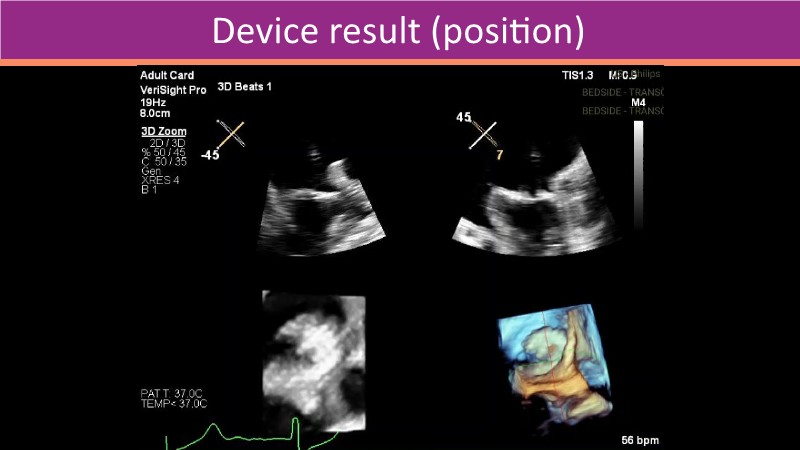

This PCR London Valves 2025 session explores how 3D TEE, 3D intracardiac echocardiography (ICE), and DeviceGuide technology sharpen procedural accuracy, strengthen operator confidence, and streamline decision-making in real time.

The session also includes detailed case analyses—such as Mitral TEER and LAA closure—and dual perspectives from both proceduralists and imagers.